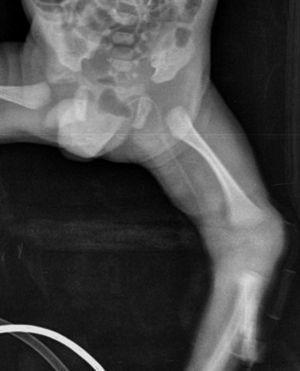

Recién nacido de 32 semanas de edad gestacional y 1.320 g de peso que ingresa en UCIN por prematuridad. Corresponde a la primera gestación controlada en madre sana. Serologías maternas negativas. En las ecografías prenatales se evidencia embarazo gemelar monocorial biamniótico sin malformaciones. Amniocentesis realizada: cariotipo XY en ambos fetos. Frotis vaginal y rectal desconocidos para Streptococcus agalactiae. Cesárea urgente a las 32 semanas por Doppler patológico del segundo gemelo y pérdidas hemáticas maternas. Amniorrexis intracesárea. Nace el primer gemelo con peso al nacimiento de 1.320 g, longitud de 40,5 cm, PC de 27 cm, Apgar 7/9 y pH de arteria umbilical 7,35. Desde sala de reanimación precisa ventilación con presión positiva continua en vía aérea (CPAP) por lo que se traslada a la UCIN. Allí se inserta un catéter sylastic central percutáneo en el miembro inferior izquierdo para iniciar la nutrición parenteral. Recibe soporte ventilatorio con CPAP (fracción inspiratoria de oxígeno [FiO2] máxima 0,30; presión máxima 7 cmH2O) y tratamiento con cafeína por apneas asociadas a la prematuridad. Se inicia antibioterapia con ampicilina y gentamicina por riesgo de infección (estado de portador materno a S. agalactiae desconocido). Al quinto día de vida se evidencia tumefacción en genitales externos con edema importante del saco escrotal (fig. 1). Se orienta inicialmente como hidrocele y se decide una actitud expectante. A las 24 h se constata una progresión de la hinchazón escrotal y edema del pene sin afectación de las extremidades inferiores ni acumulación de líquido en otras localizaciones. El saco escrotal es blando a la palpación y no parece doloroso, la transiluminación demuestra líquido en su interior y en la piel escrotal se observa una pequeña herida con mínima solución de continuidad y bordes eritematosos. Inicialmente se orienta el cuadro como una sospecha clínica de infección con puerta de entrada cutánea. Se extrae hemocultivo y se inicia antibioterapia empírica con teicoplanina y ceftazidima. La analítica no evidencia alteración en los parámetros de infección. Revisando la radiografía realizada para control del sylastic central percutáneo se observa que el trayecto de éste llega tortuosamente hasta la zona escrotal (fig. 2). Dada la sospecha de introducción del catéter hasta los vasos espermáticos a través de la vena ilíaca con obstrucción del flujo venoso y posterior acumulación de líquido, se decide retirar el catéter sylastic. A las 12 h de la retirada del mismo desaparece la tumefacción escrotal y el pene vuelve a tener un aspecto totalmente normal. El resultado del hemocultivo es negativo por lo cual se suspende la antibioterapia a los 3 días. Evolución posterior sin incidencias.

Figura 2. Radiografía que muestra el trayecto del catéter.